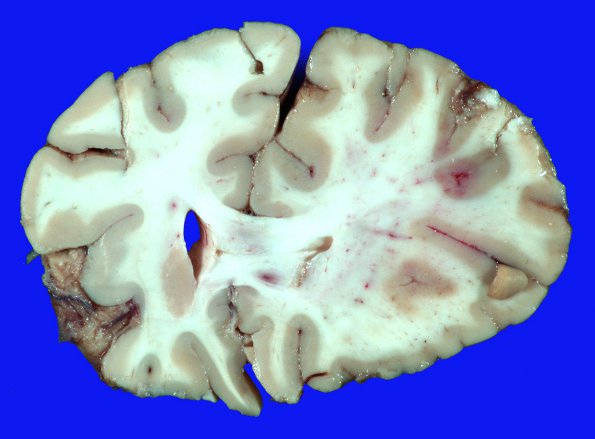

Washington University Experience | VASCULAR | Infarct - Embolic | 20A1 Catheter Sheath Emboli (Case 20)

This is a coronal section of the infarcted frontal lobes in this patient. The infarct was not caused by the hydrophilic material to be shown but was admixed within the microscopic areas of infarction.